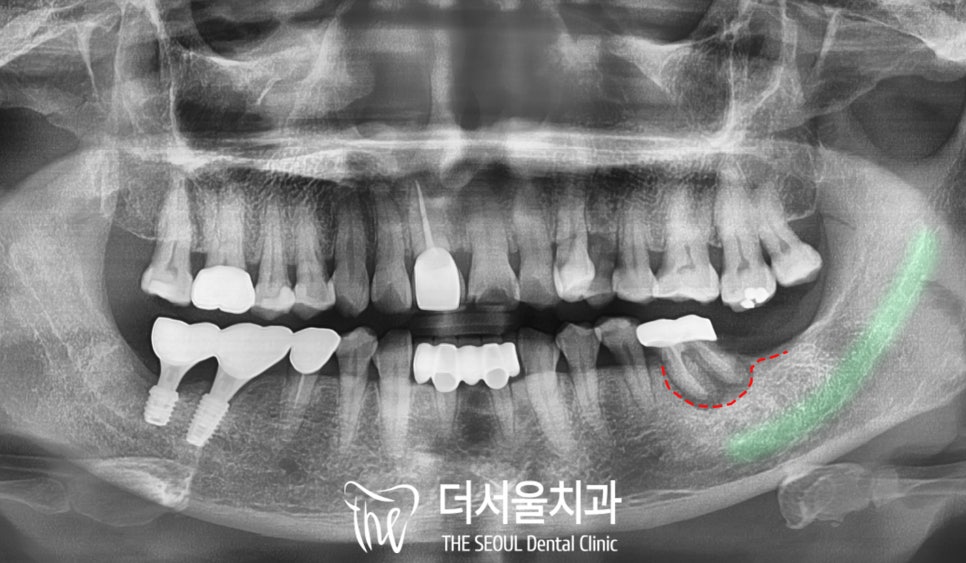

2. 파노라마 엑스레이 분석

태평역치과 에서

파노라마 엑스레이를 찍어보니

치아를 감싸고 있는

치조골에 염증이 생겨

녹아있었습니다.

이게 무엇을 뜻하는 걸까요?

흔히 ‘잇몸이 내려갔다’

라고 말하긴 하는데요,

간단히 말해 우리 구강은

잇몸뼈(=치조골)가

치아를 단단하게 잡아주는 구조인데,

이렇게 염증이 생기게 되면

그 주변 치주조직들이 녹아서 흡수됩니다.

그렇기에 음식을 먹을때 필요한

어금니의 힘을 버티기 어려운 수준까지

이르게 되고,

그러다 보면 이가 흔들리고

불편함이 생길 수 있습니다.

잇몸뼈가 녹는 이유 중에서

많이 언급되는 것은

‘치주염’ 이 있습니다.

치아 주위 조직에 영향을 주는

염증 질환으로

치근을 둘러싸고 있는 뼈가

점차 소실되면서

제때 치료하지 못하면

결국 발치까지 이어질 수 있죠.

이 케이스에서도 뿌리 끝까지

진행된 치주 질환으로

발치를 판정했습니다.